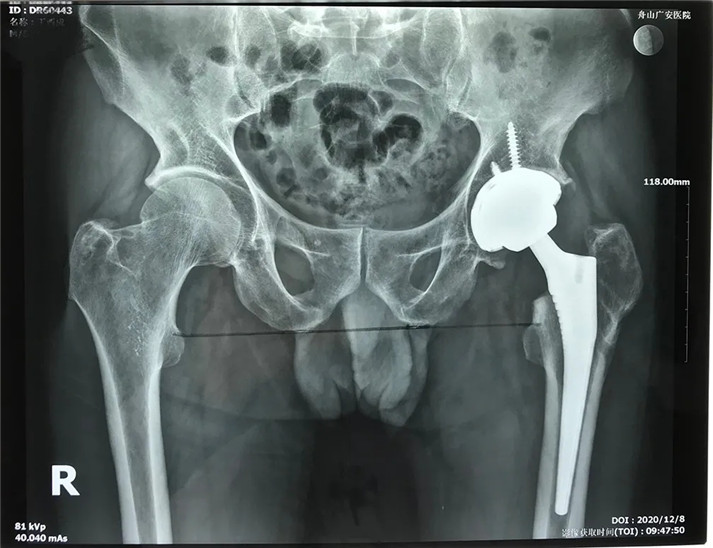

結(jié)合影像學(xué)表現(xiàn)研究后,骨科中心羅軍主任診斷丁先生為左股骨頭壞死,并建議其行全髖關(guān)節(jié)置換手術(shù)。

經(jīng)過(guò)周密的術(shù)前準(zhǔn)備,在身體符合手術(shù)指征后,丁大哥接受了全髖關(guān)節(jié)置換術(shù)。術(shù)中發(fā)現(xiàn)術(shù)前規(guī)劃產(chǎn)生的假體大小、位置、角度均非常理想,大大縮短了手術(shù)時(shí)間,全程十分順利。術(shù)后,丁先生恢復(fù)良好,次日即可下床活動(dòng)。目前術(shù)后一個(gè)月,可以干活了。對(duì)于此次手術(shù),丁大哥及其家屬表示非常滿意。

術(shù)后